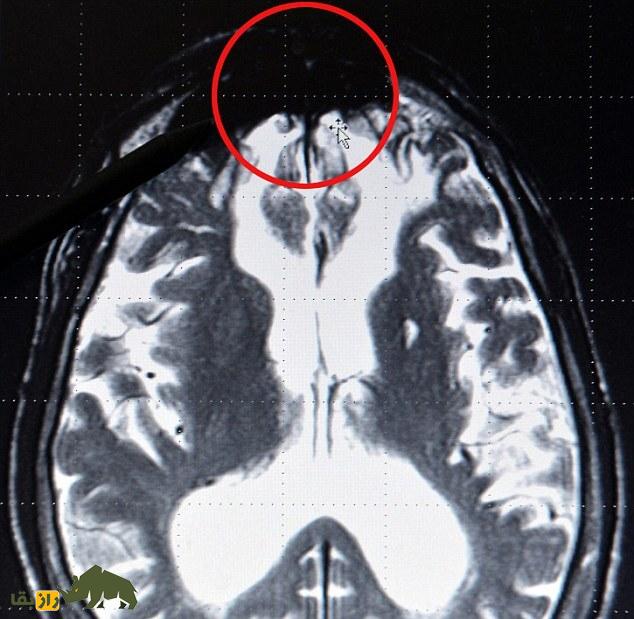

به گزارش راز بقا؛ دکتر «جرارد راث» اظهار کرده که وصله شر در لوب مرکزی مغزی قرار داشته و در تابشهای ایکس به شکل یک توده سیاه مشخص میشود. راث این منطقه را در زمان بررسی مجرمین جرائم خشونتآمیز محکوم در طول سالها پژوهش برای دولت آلمان شناسایی کرده است.

به گفته راث، اسکنهای افراد دارای سوابق خشونت جنایی، توده تاریکی در جلوی مغز را نشان میدهد که وی بر اساس آنها مدعی شده که برخی از مجرمین از زمینه ژنتیکی برای خشونت برخوردارند.

راث افزود: هنگامی که به اسکنهای مغزی صدها مجرم مینگرید، تقریبا همیشه کمبودهای شدیدی در بخش پیشانی پایینتر مغز وجود دارد. مواردی بوده که شخص در نتیجه یک تومور یا آسیب در این منطقه مجرم شده و پس از عمل جراحی برای برداشتن تومور، فرد به حالت عادی بازگشته است.

وی اظهار کرد: همچنین ممکن است کمبودهای فیزیولوژیکی وجود داشته باشد؛ چرا که مواد خاصی مانند سروتونین در جلوی مغز به شکل موثر کار نمیکنند؛ اما مسلما این منطقه جایی است که شر در آن شکل گرفته و فعالیت میکند.